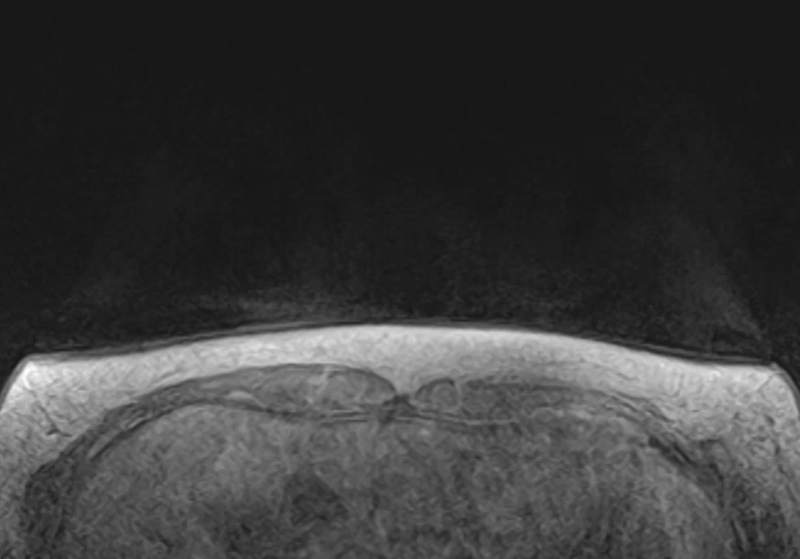

2.乳腺磁共振检查(MRI):高端技术,精准评估。

对于高危人群或复杂病例来说,乳腺磁共振检查则提供了更为精准、立体的图像信息。它能够全方位、多角度地展示乳腺内部的病灶情况,提供精准诊断,为我们制定个性化的治疗方案提供了有力依据。

磁共振正常乳腺的图像